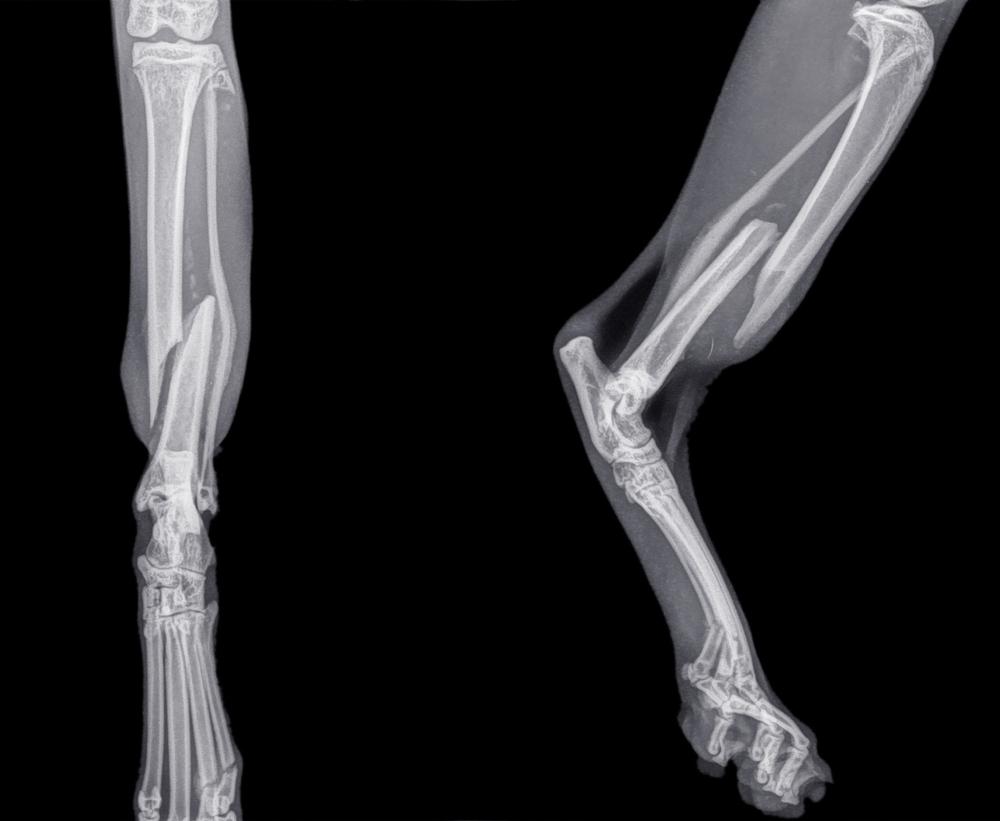

В первую очередь потребуется сделать рентген. Этот способ самый информативный, но предполагает обязательное использование общего наркоза. Кроме него, могут потребоваться анализы мочи и крови, УЗИ брюшной полости и сердца, КТ и МРТ. Если животное находится в тяжелом состоянии, то его оставляют в стационаре до стабилизации самочувствия.